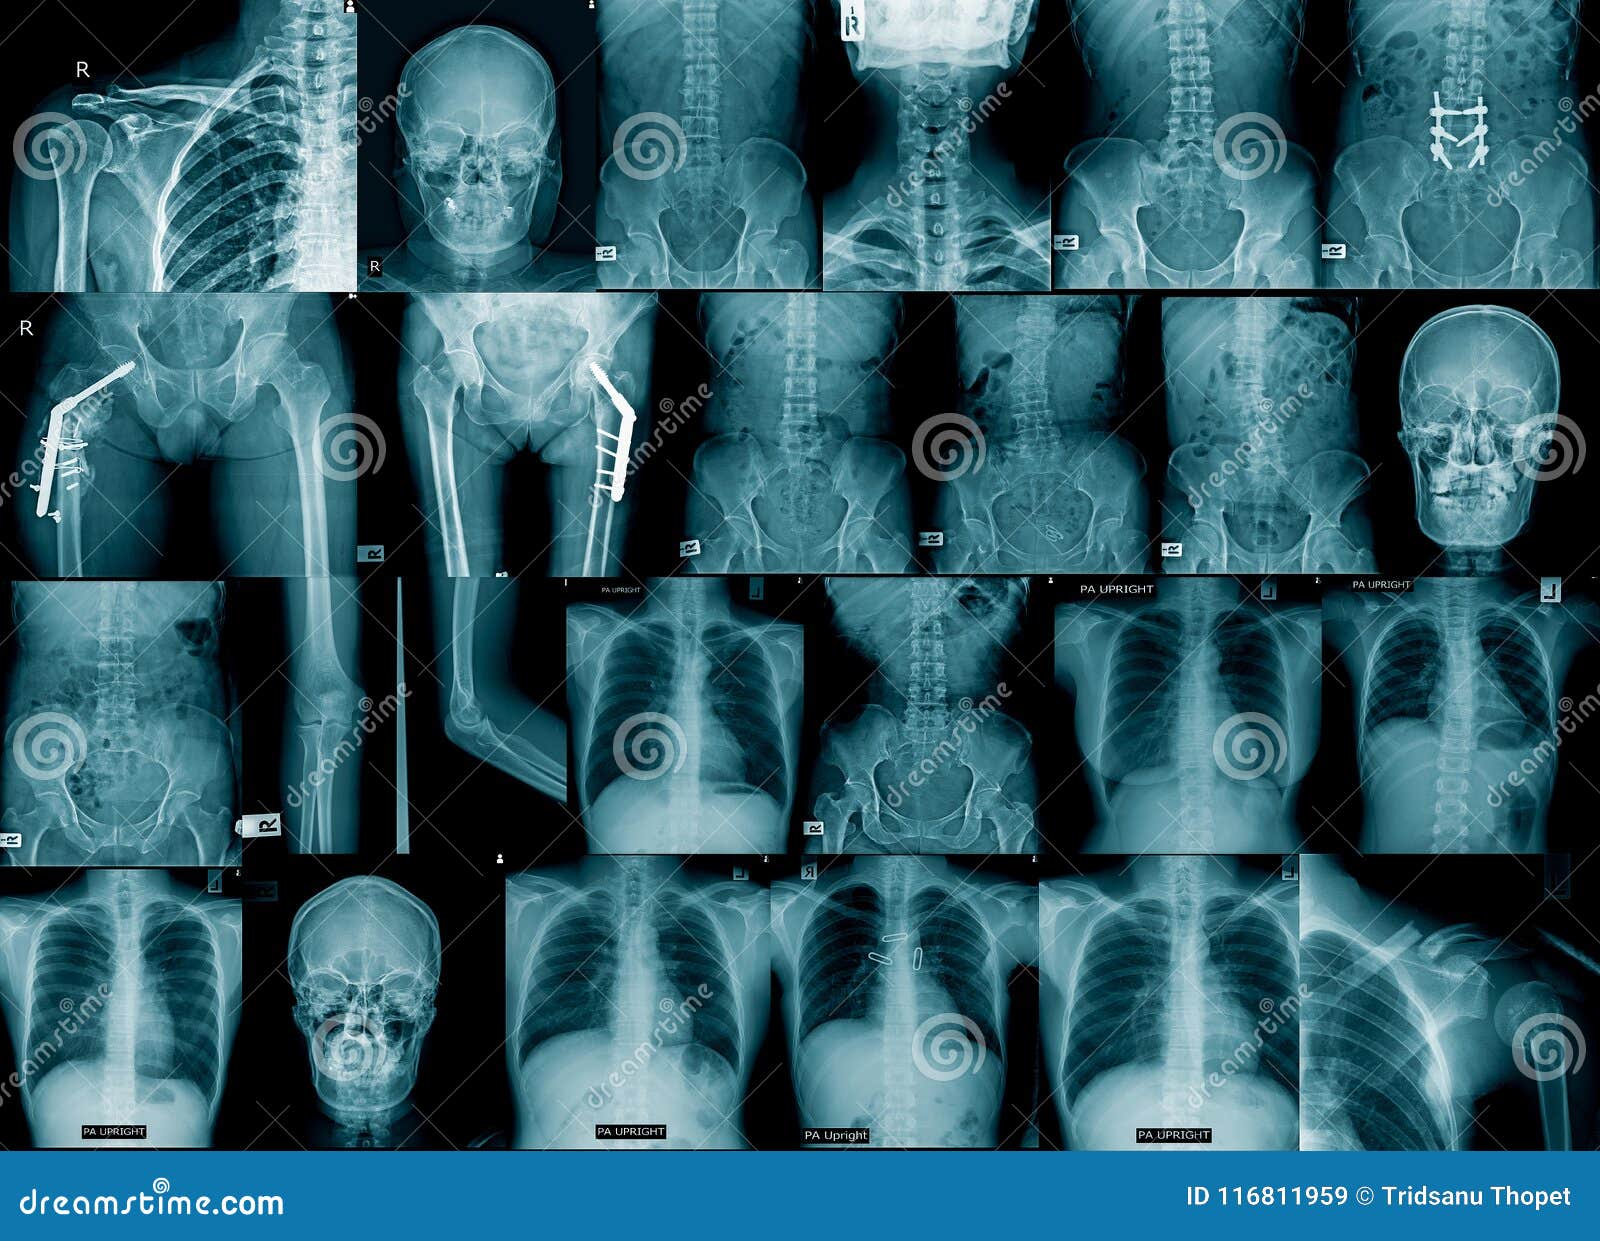

collection Chest Xray or XRay Image Of Human AP and both oblique view Fracture X Ray Chest the chest is normal on auscultation. chest radiographs (all patients) — in patients with suspected rib fractures or chest wall trauma, chest radiographs (cxrs). Should this patient undergo imaging to determine if he has a rib fracture? fractures of the sternum can result from both direct and indirect blunt force trauma to the chest with motor vehicle. Fracture X Ray Chest.

From www.svuhradiology.ie